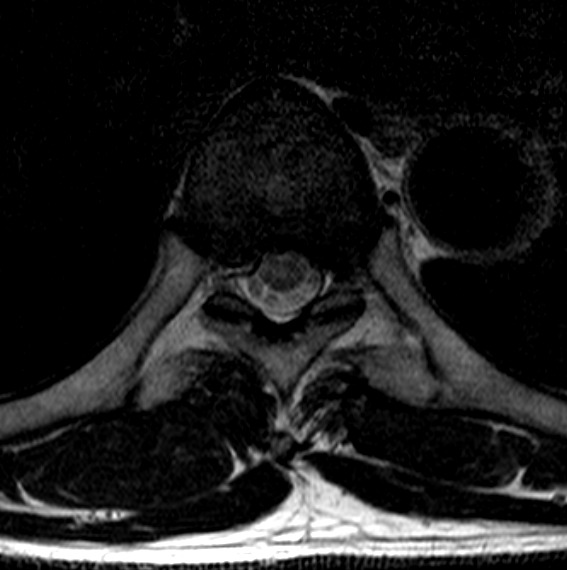

3. T2 Axial에서의 척수 영역 분할 및 면적 측정 모델

- 모델 학습

- 바이오 의료 영상 분야에서 분할을 목적으로 만들어진 모델을 사용하여 학습을 진행.

- Erode 및 Dilate, Median Blur를 이용해 이미지 후처리. Noise 및 Hole 제거

[T2 MRI에서 척수 영역 분할 모델 개요]

경추 각 추체에 대한 bounding boxT2 axial image에서 흉추5-6번 구간의 면적

T2 axial image에서 척수 영역에 대한 외곽선흉추골화증평가